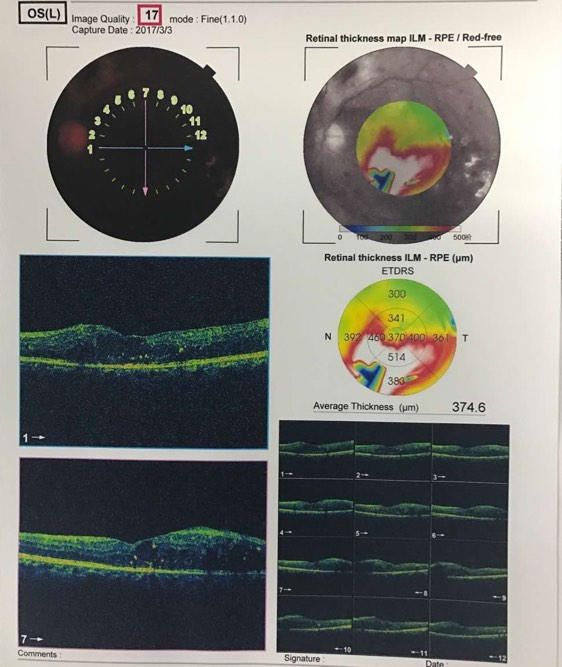

糖尿病视网膜病变引起的黄斑水肿中医有什么好的法子?西医打针输液已经治疗中,可是水肿还是下不来,急。。。